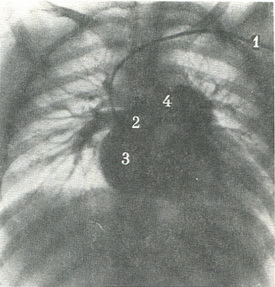

На прямій ангиограмме a. pulmonalis має довжину 3 см, діаметр 2 - 3 см і накладається на тінь хребта на рівні VI грудного хребця. Тут вона поділяється на праву і ліву гілки. Потім можна диференціювати всі сегментарні артерії. Вени верхньої і середньої часток з'єднуються в верхню легеневу вену, має косе положення, а вени нижньої частки - в нижню легеневу вену, розташовану горизонтально по відношенню до серця (рис. 314, 315).

![]() 314. Артеріальна фаза при загальній ангиопульмонографии. Катетер (1) проведено до правого передсердя. Контрастированы праве передсердя (2), правий шлуночок (3), легенева артерія (4) і її гілки в обох легенях (по Л. Д. Линденбратену).  |